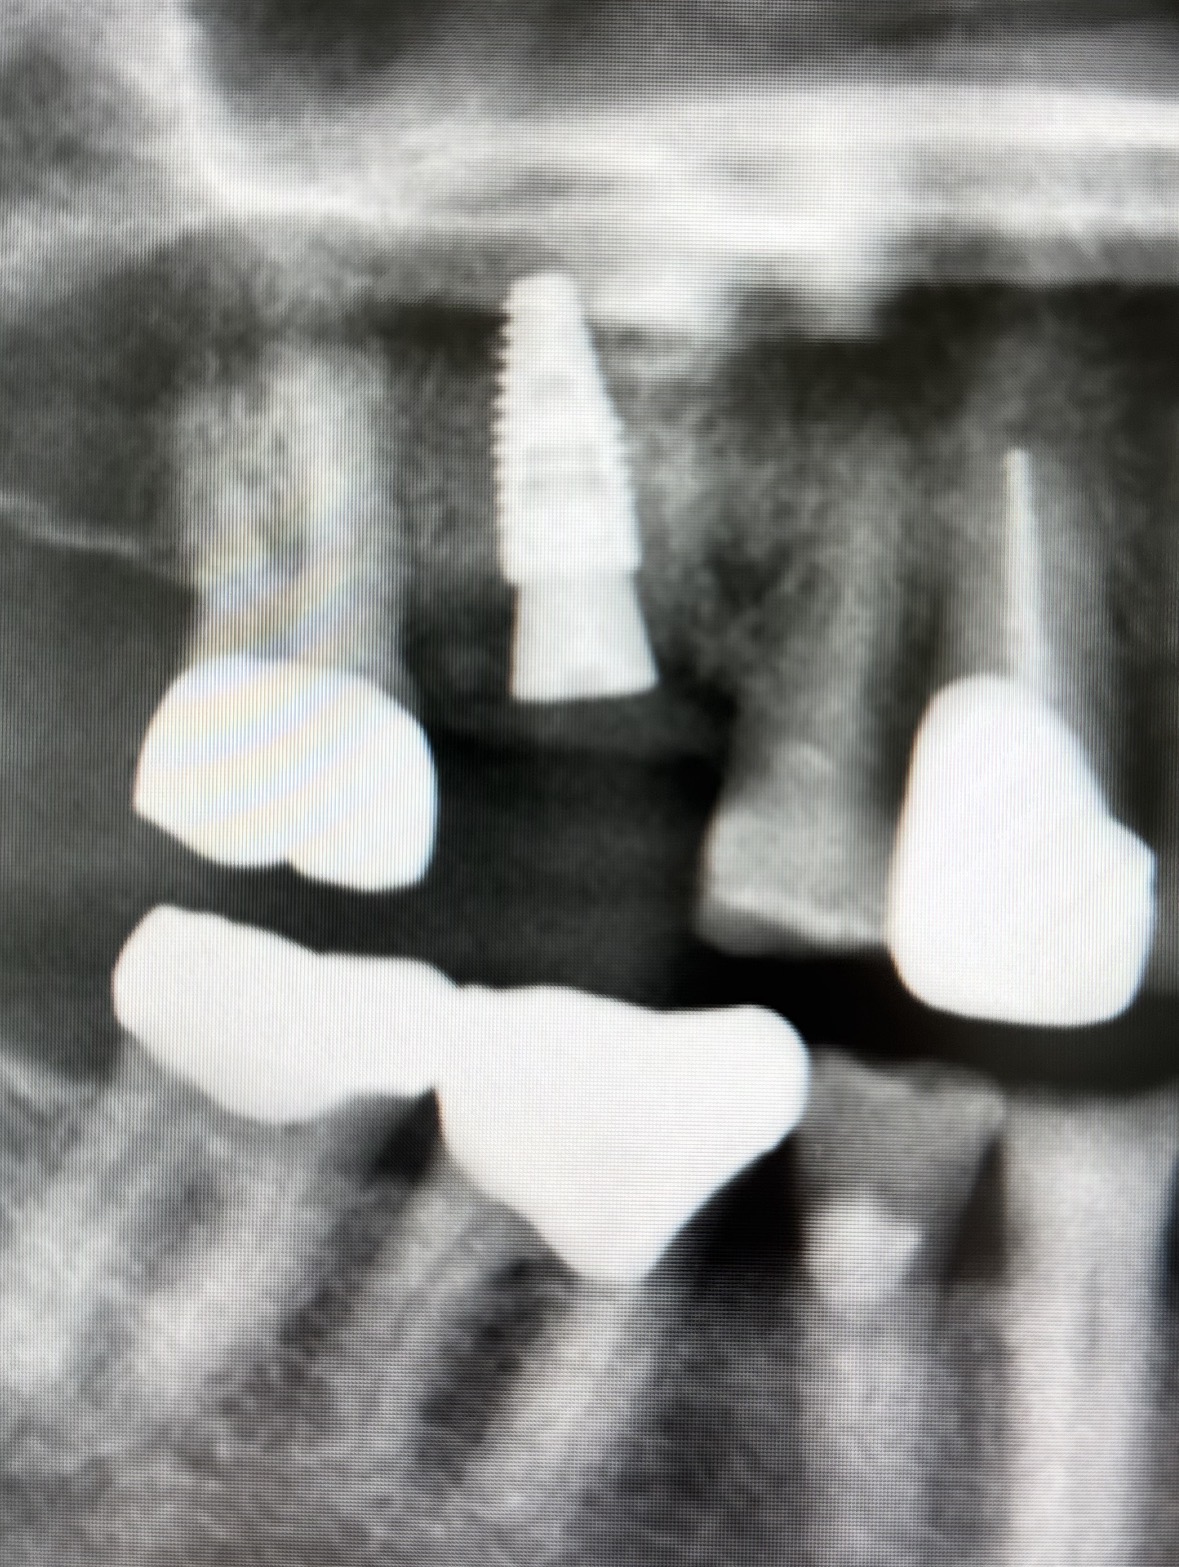

Would like feedback on implant #3. Angulation is not ideal but still restorable.

Would an angled abutment probably be required?

i think you should be fine w/ a screw retained straight stock abutment

the access hole will be more mesial but should be fine.

the angulation is not the best but should be restorable w/ a straight stock (prefab) abutment. IMO